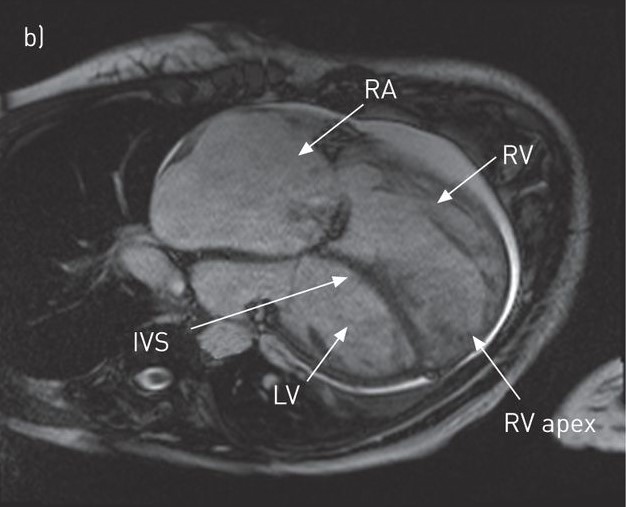

However, some researchers [15, 32] have shown that well-trained models do not perform well when the testing images come from a different statistical distribution from the training images. This domain shift problem is common in real-world medical diagnosis since medical images at various steps of the clinical procedure are often obtained with different physical properties [6]. For instance, Magnetic Resonance Imaging (MRI) and Computed Tomography (CT) play complementary roles in cardiac disease diagnosis while also exhibiting different appearances (See Fig. 1). That difference post challenges for analyzing the MRI and CT images in clinical diagnosis.

MM-WHS Dataset contains 20 labeled CT 3D images and 20 labeled MRI 3D images, which are unpaired. The original size of all images is 240220, which are cropped with a Region of Interest (ROI) of 192 × 192.

Similar to [33, 34], we include the following three structures in MS-CMRSeg dataset for segmentation: the myocardial (MYO), the left ventriculus (LV), and the right ventriculus (RV). In MM-WHS Dataset, we include five structures: the myocardial (MYO), the left ventriculus (LV), the right ventriculus (RV), the left atrium blood cavity (LA), and the right atrium blood cavity (RA). For both datasets, We remove the LGE-MRI ground truth during bSSFP to LGE-MRI experiments, remove the bSSFP ground truth during LGE-MRI to bSSFP, and remove the MRI ground truth during CT to MRI experiments. The train-test split strategy is consistent with [5, 2, 33, 34]